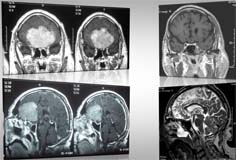

Adenoma ipofisario

L’adenoma ipofisario è un tumore benigno che si sviluppa dall’ipofisi, una piccola ghiandola che si trova all’interno del cranio dentro la sella turcica.

L’ipofisi, tramite la produzione di ormoni è deputata al controllo di tutte le altre ghiandole dell’organismo e quindi svolge un’azione di modulazione di tutte le funzioni vitali: dalla crescita allo sviluppo degli organi sessuali, dallo sviluppo neuropsichico alla risposta agli stress.

Gli adenomi ipofisari possono essere “secernenti”, quando producono ormoni, o “non secernenti”. A seconda delle dimensioni si parla di microadenomi (<1 cm) o macroadenomi (>1 cm).

I sintomi possono essere variabili e associati al tipo di ormone prodotto (alterazione del ciclo mestruale, riduzione della libido, diabete, ipertensione...). Altri sintomi invece sono dovuti all’effetto massa del tumore sulle strutture circostanti ed in particolare sui nervi ottici o sul chiasma ottico con conseguenti disturbi del campo visivo. Durante la sua crescita l’adenoma può comprimere il seno cavernoso dove decorre la carotide e alcuni nervi cranici che regolano i movimenti dei muscoli oculari con conseguente diplopia (visione doppia). In alcuni casi gli adenomi possono sanguinare e manifestarsi con violenta cefalea e amaurosi (perdita transitoria o definitiva della vista).